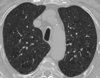

Histiocytose X

Association

- Nodules irréguliers centrolobulaires

- Nodules troués

- Kystes

Prédominance régions supérieures